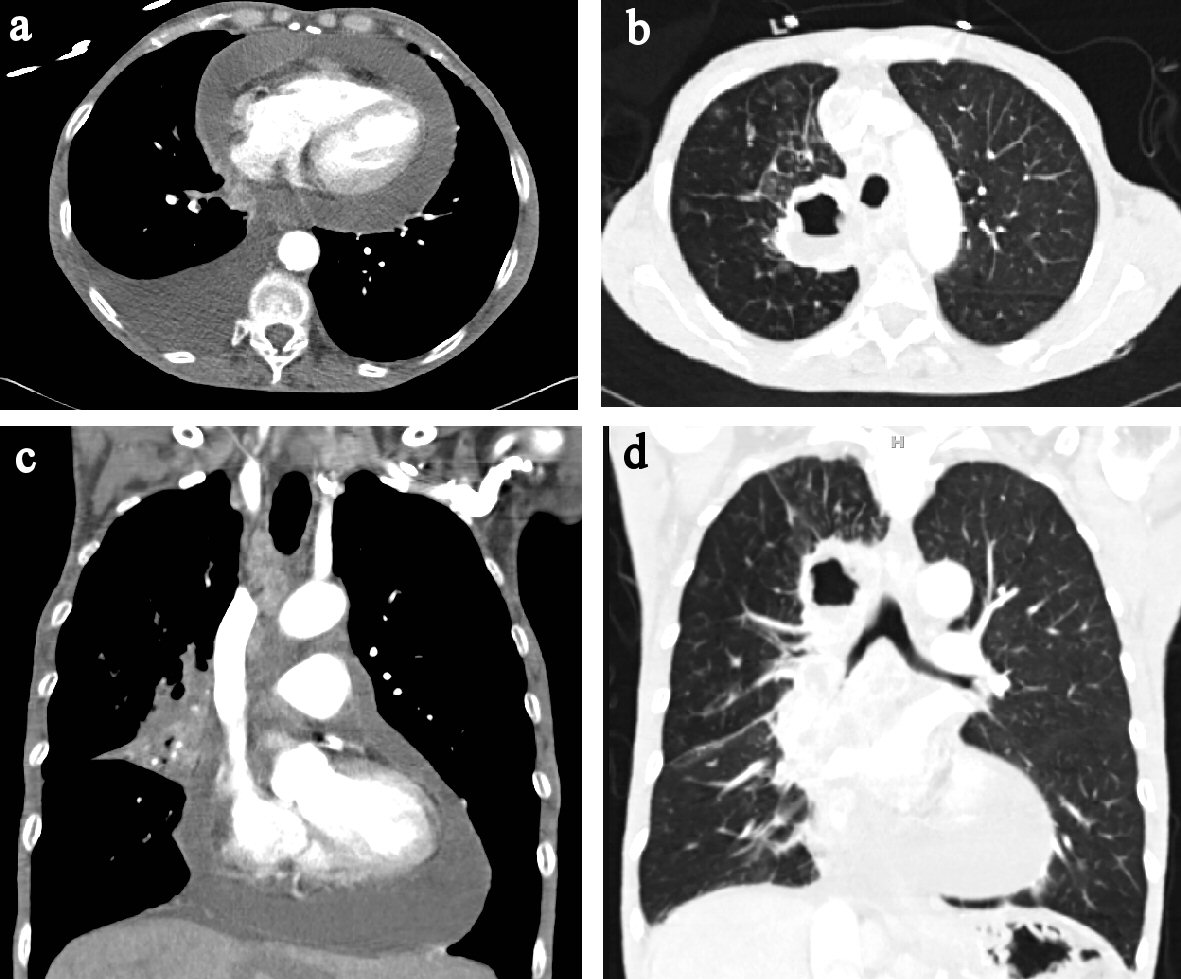

Figure 7. (a) CT chest axial view showing pericardial effusion. (b) CT chest axial view showing in pulmonary window showing air filled cavity with air-fluid level. (c) CT chest coronal view showing pericardial effusion. (d) CT chest coronal view in pulmonary window.